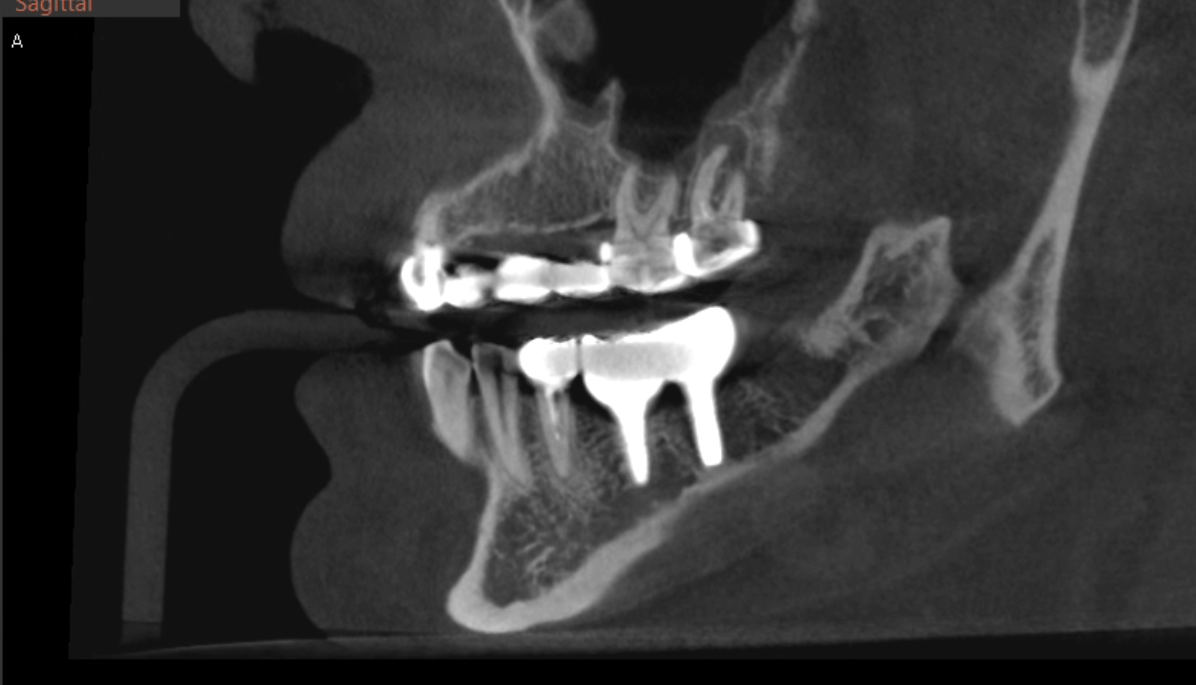

КТ 2.7 зуба до лечения

Печально, что тканей осталось мало.

Фуркация - особая зона. Когда она вовлечена в патологический процесс, прогноз зуба резко ухудшается. В домашних условиях фуркационную зону, практически, не очистить качественно. Это означает риски для кости, связанные с микробной биоплёнкой.

Ортопедический прогноз у зуба откровенно сомнительный. Долго Роман Юрьевич консультировался с ортопедом клиники Мингияном Юрьевичем, крепко думали врачи - оставлять или удалять? Решили не торопиться - сделать диагностическое препарирование и посмотреть, что там на самом деле с зубом происходит. Иногда реальность оказывается чуть лучше и перспективнее, чем показывает снимок рентгенологический.